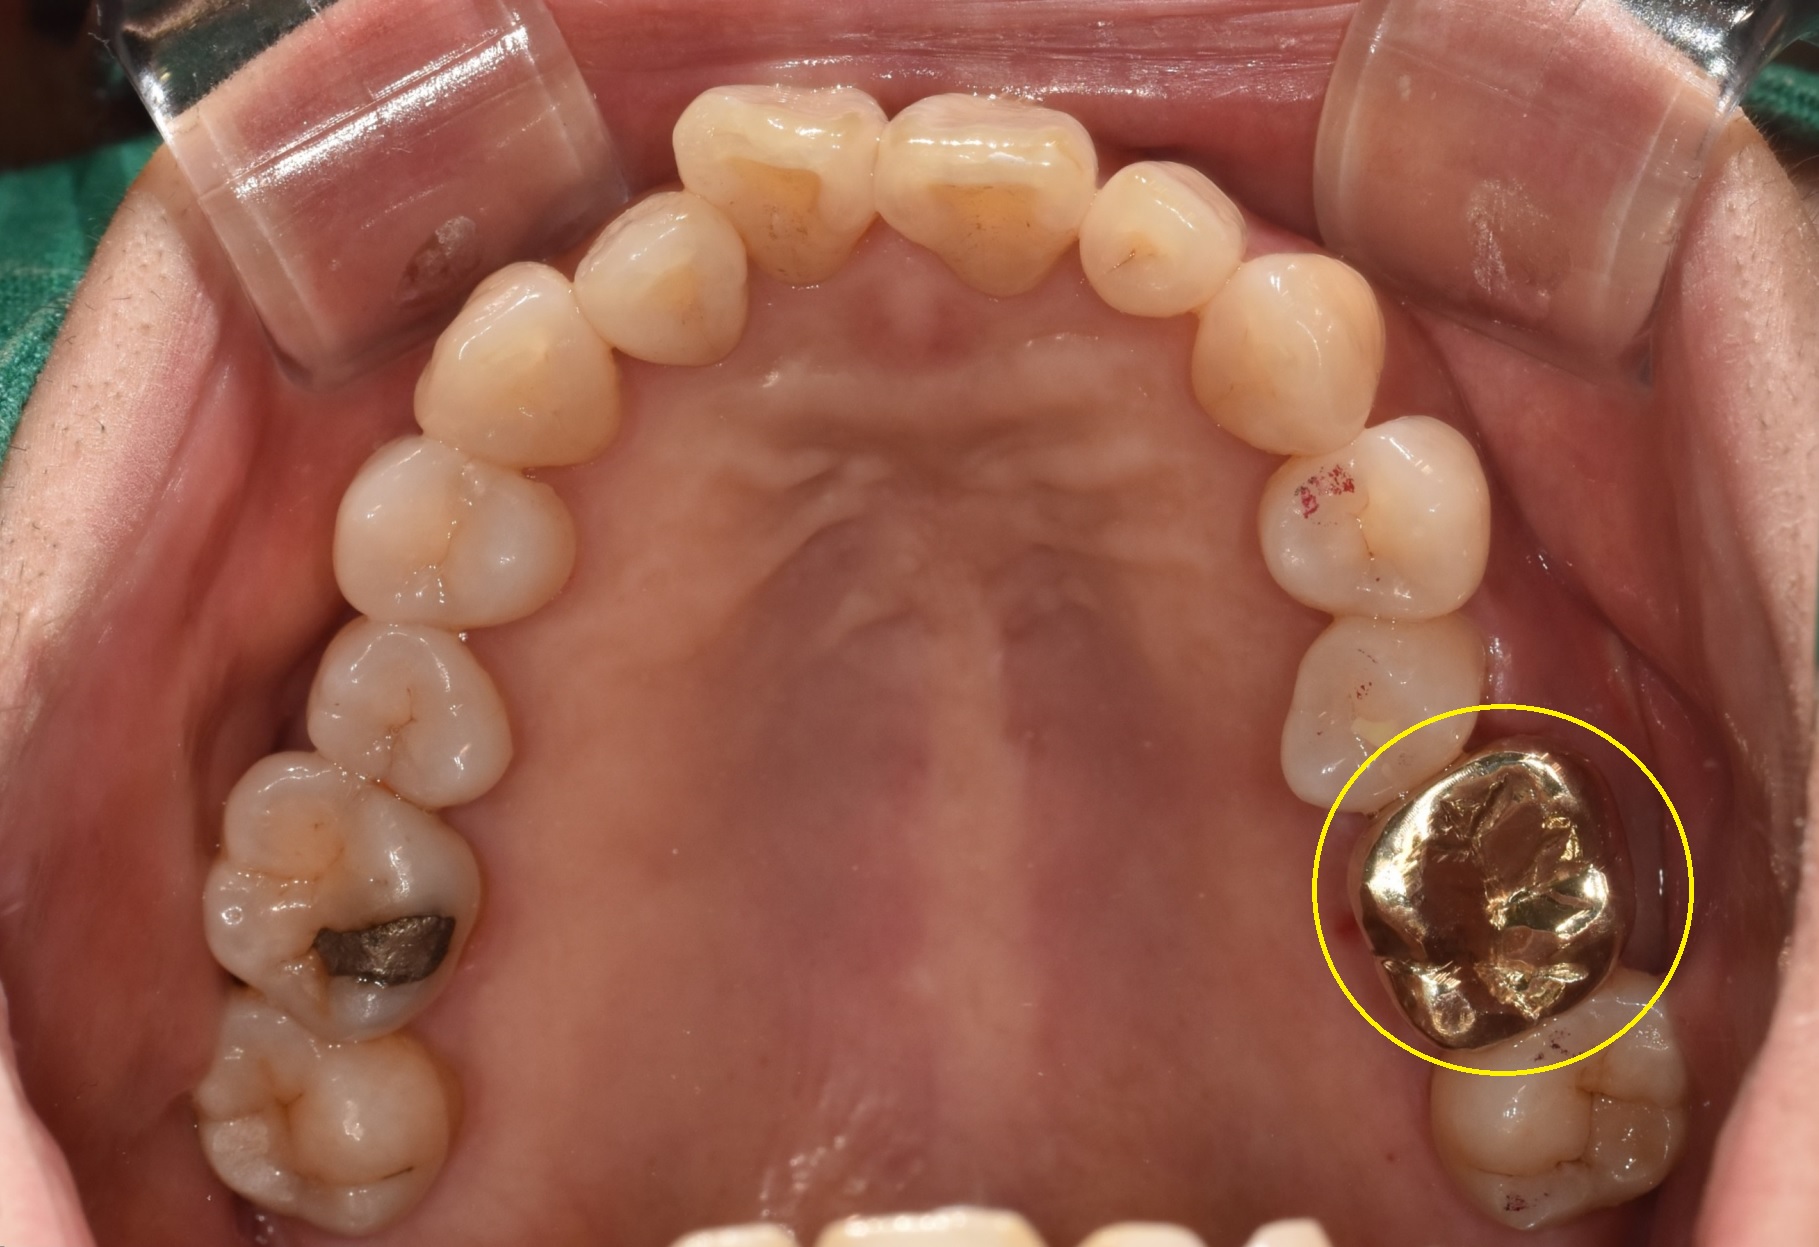

아직까지는 논란이 조금은 있지만 개인적으로는 특히나 파절, 혹은 크랙 치아에서는 Gold crown이 가장 잘 어울린다고 생각합니다.

다행히 환자분께서 제 의견을 잘 이해해 주셔서 Gold crown으로 마무리한 모습입니다.